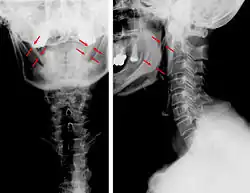

CT scan, coronal section showing bilateral extended styloid process and stylohyoid ligament ossification (incidental finding) -

3D-reconstructed CT scan showing bilateral stylohyoid ligament ossification -

Diagnosis is suspected when a patient presents with the symptoms of the classic form of "Eagle syndrome" e.g. unilateral neck pain, sore throat or tinnitus. Sometimes the tip of the styloid process is palpable in the back of the throat. The diagnosis of the vascular type is more difficult and requires an expert opinion. One should have a high level of suspicion when neurological symptoms occur upon head rotation. Symptoms tend to be worsened on bimanual palpation of the styloid through the tonsillar bed. They may be relieved by infiltration of lidocaine into the tonsillar bed. Because of the proximity of several large vascular structures in this area this procedure should not be considered to be risk free.

Imaging is important and is diagnostic. Visualizing the styloid process on a CT scan with 3D reconstruction is the suggested imaging technique.[13] The enlarged styloid may be visible on an orthopantogram or a lateral soft tissue X ray of the neck.